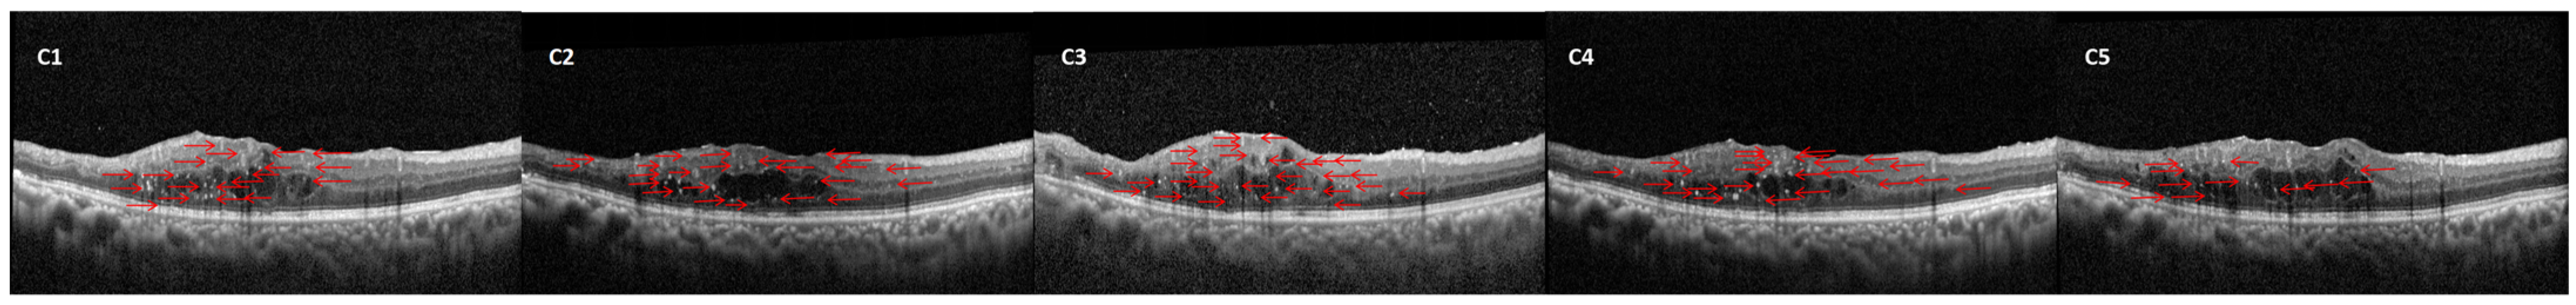

In this study, 112 eyes from 78 patients diagnosed with diabetic macular edema (DME) were included for analysis. Among these, 73 eyes (65%) demonstrated a positive response to ranibizumab treatment, as determined by predefined clinical criteria such as improved best-corrected visual acuity (BCVA) and reduced central retinal thickness (CRT) (Figure 1). In contrast, 39 eyes (35%) did not show a well-defined response, failing to meet these key improvement benchmarks. The 39 eyes that responded poorly to ranibizumab were subsequently treated with an intravitreal dexamethasone implant. Following this intervention, 26 eyes (66.67%) achieved a favorable outcome (Figure 2), while 13 eyes (33.33%) continued to exhibit a poor response to the treatment (Figure 3).

Figure 1. Example case of DME successfully treated with ranibizumab. The initial observation (A1) reveals a small number of hyperreflective dots (HRDs) (red arrow) alongside increased thickness of the central macular region (CMT). Post-injection evaluations (A2A4) demonstrate a continuing decrease in CMT and HRDs.